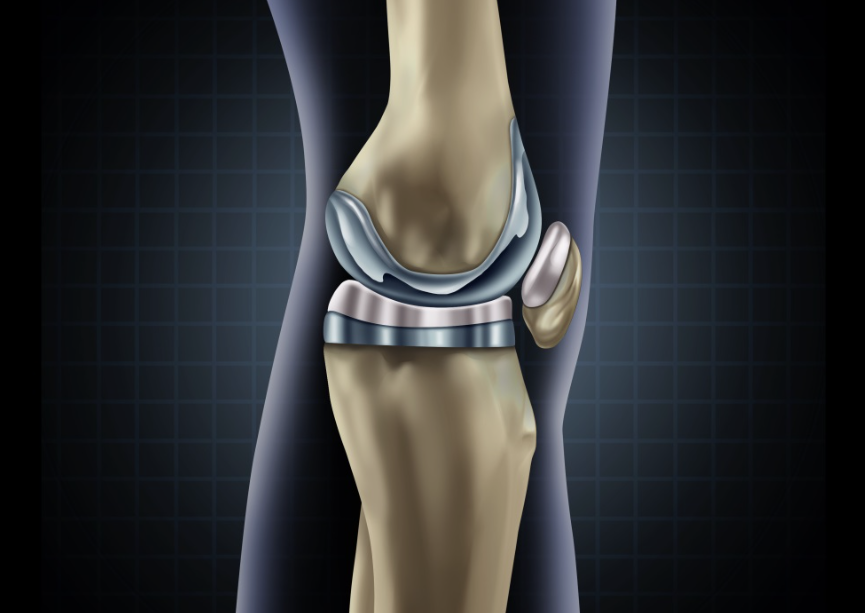

Diz Protezi Ameliyatı

Diz protezi ameliyatı, diz eklemindeki hasarlı veya aşınmış dokuların çıkarılması ve yapay bir protez ile değiştirilmesini içeren bir cerrahi prosed&uu...

Robotik Diz Protezi Ameliyatı

Robotik Diz Protezi Ameliyatı, son yıllarda geliştirilen bir teknoloji ile yapılan bir cerrahi prosedürdür. Bu prosedür, diz ekleminde ağrı, kireçlen...